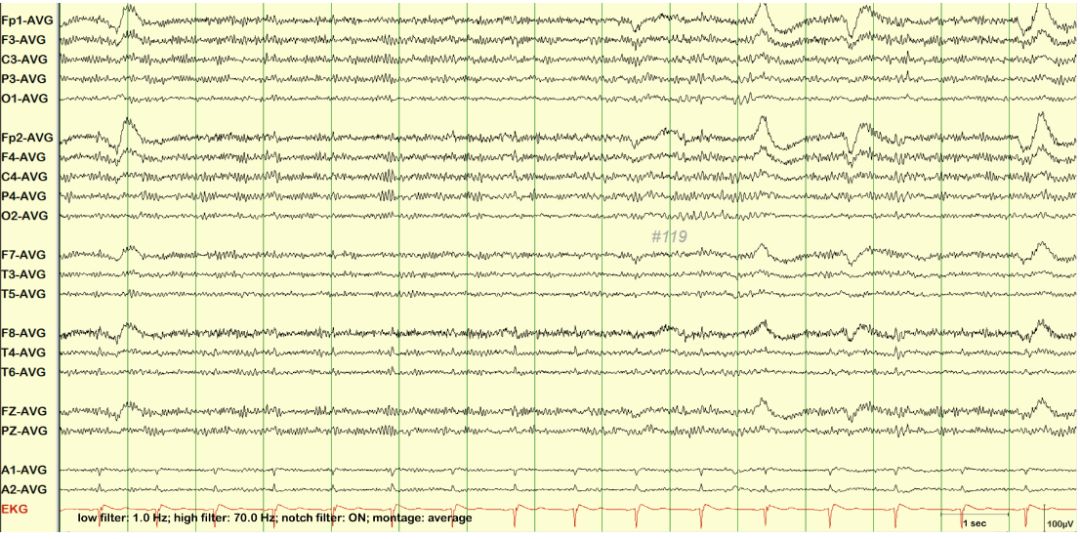

1. 心电伪差

心电信号的电压为毫伏级(mV),比微伏级(uV)的脑电信号强一个数量级,当心电信号通过容积导体效应,在体表的大多数部位均可记录到,很容易传导到脑电的任何一个参考电极或记录电极部位。当心电信号干扰某一个或几个记录电极时,可见相应导联出现间隔大致相同,且与心率一致的正相或负相尖样波(见图1-1、1-2、1-3、1-4)。

未标注脑电图 图1-1

标注脑电图 图1-2心电伪差

未标注脑电图 图1-3

标注脑电图 图1-4心电伪差

与心电同步表现出突出于左耳电极A1处的心电伪差。